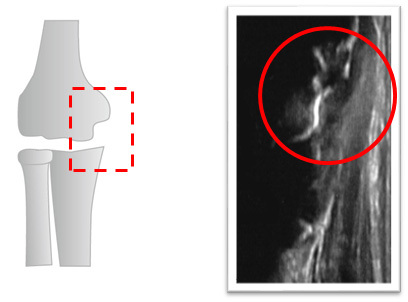

成長期に起こる野球肘の1つである上腕骨内側上顆剥離骨折は少年野球の選手に多く起こるスポーツ傷害です。

肘の内側に痛みがあり、投球することができなくなる傷害です。

野球肘は成長期にしっかり治しておかない骨が変形してしまい、将来的に手術をすることになってしまうこともあります。

成長期に起こる野球肘(上腕骨内側上顆剥離骨折)は経過をしっかり観察して治療していくことが大切です。

痛みが無くなり投球を開始しても再発することが多くあります。

その原因は骨の癒合が終わっていないまま投球を開始したことにあります。

エコー検査を使用することで再発を防止することができます。

上記の例では1ヶ月で骨の癒合が始まったことが確認できます。3ヶ月で骨の癒合が最終段階にあるのでキャッチボールを開始し、4ヶ月で骨の癒合が終了したので試合に参加しました。その後、肘が痛くなることはなく野球を続けています。

経過観察を定期的に行うことで、固定の解除やリハビリ、運動の開始を判断することができ、早期復帰を目指すことができます。